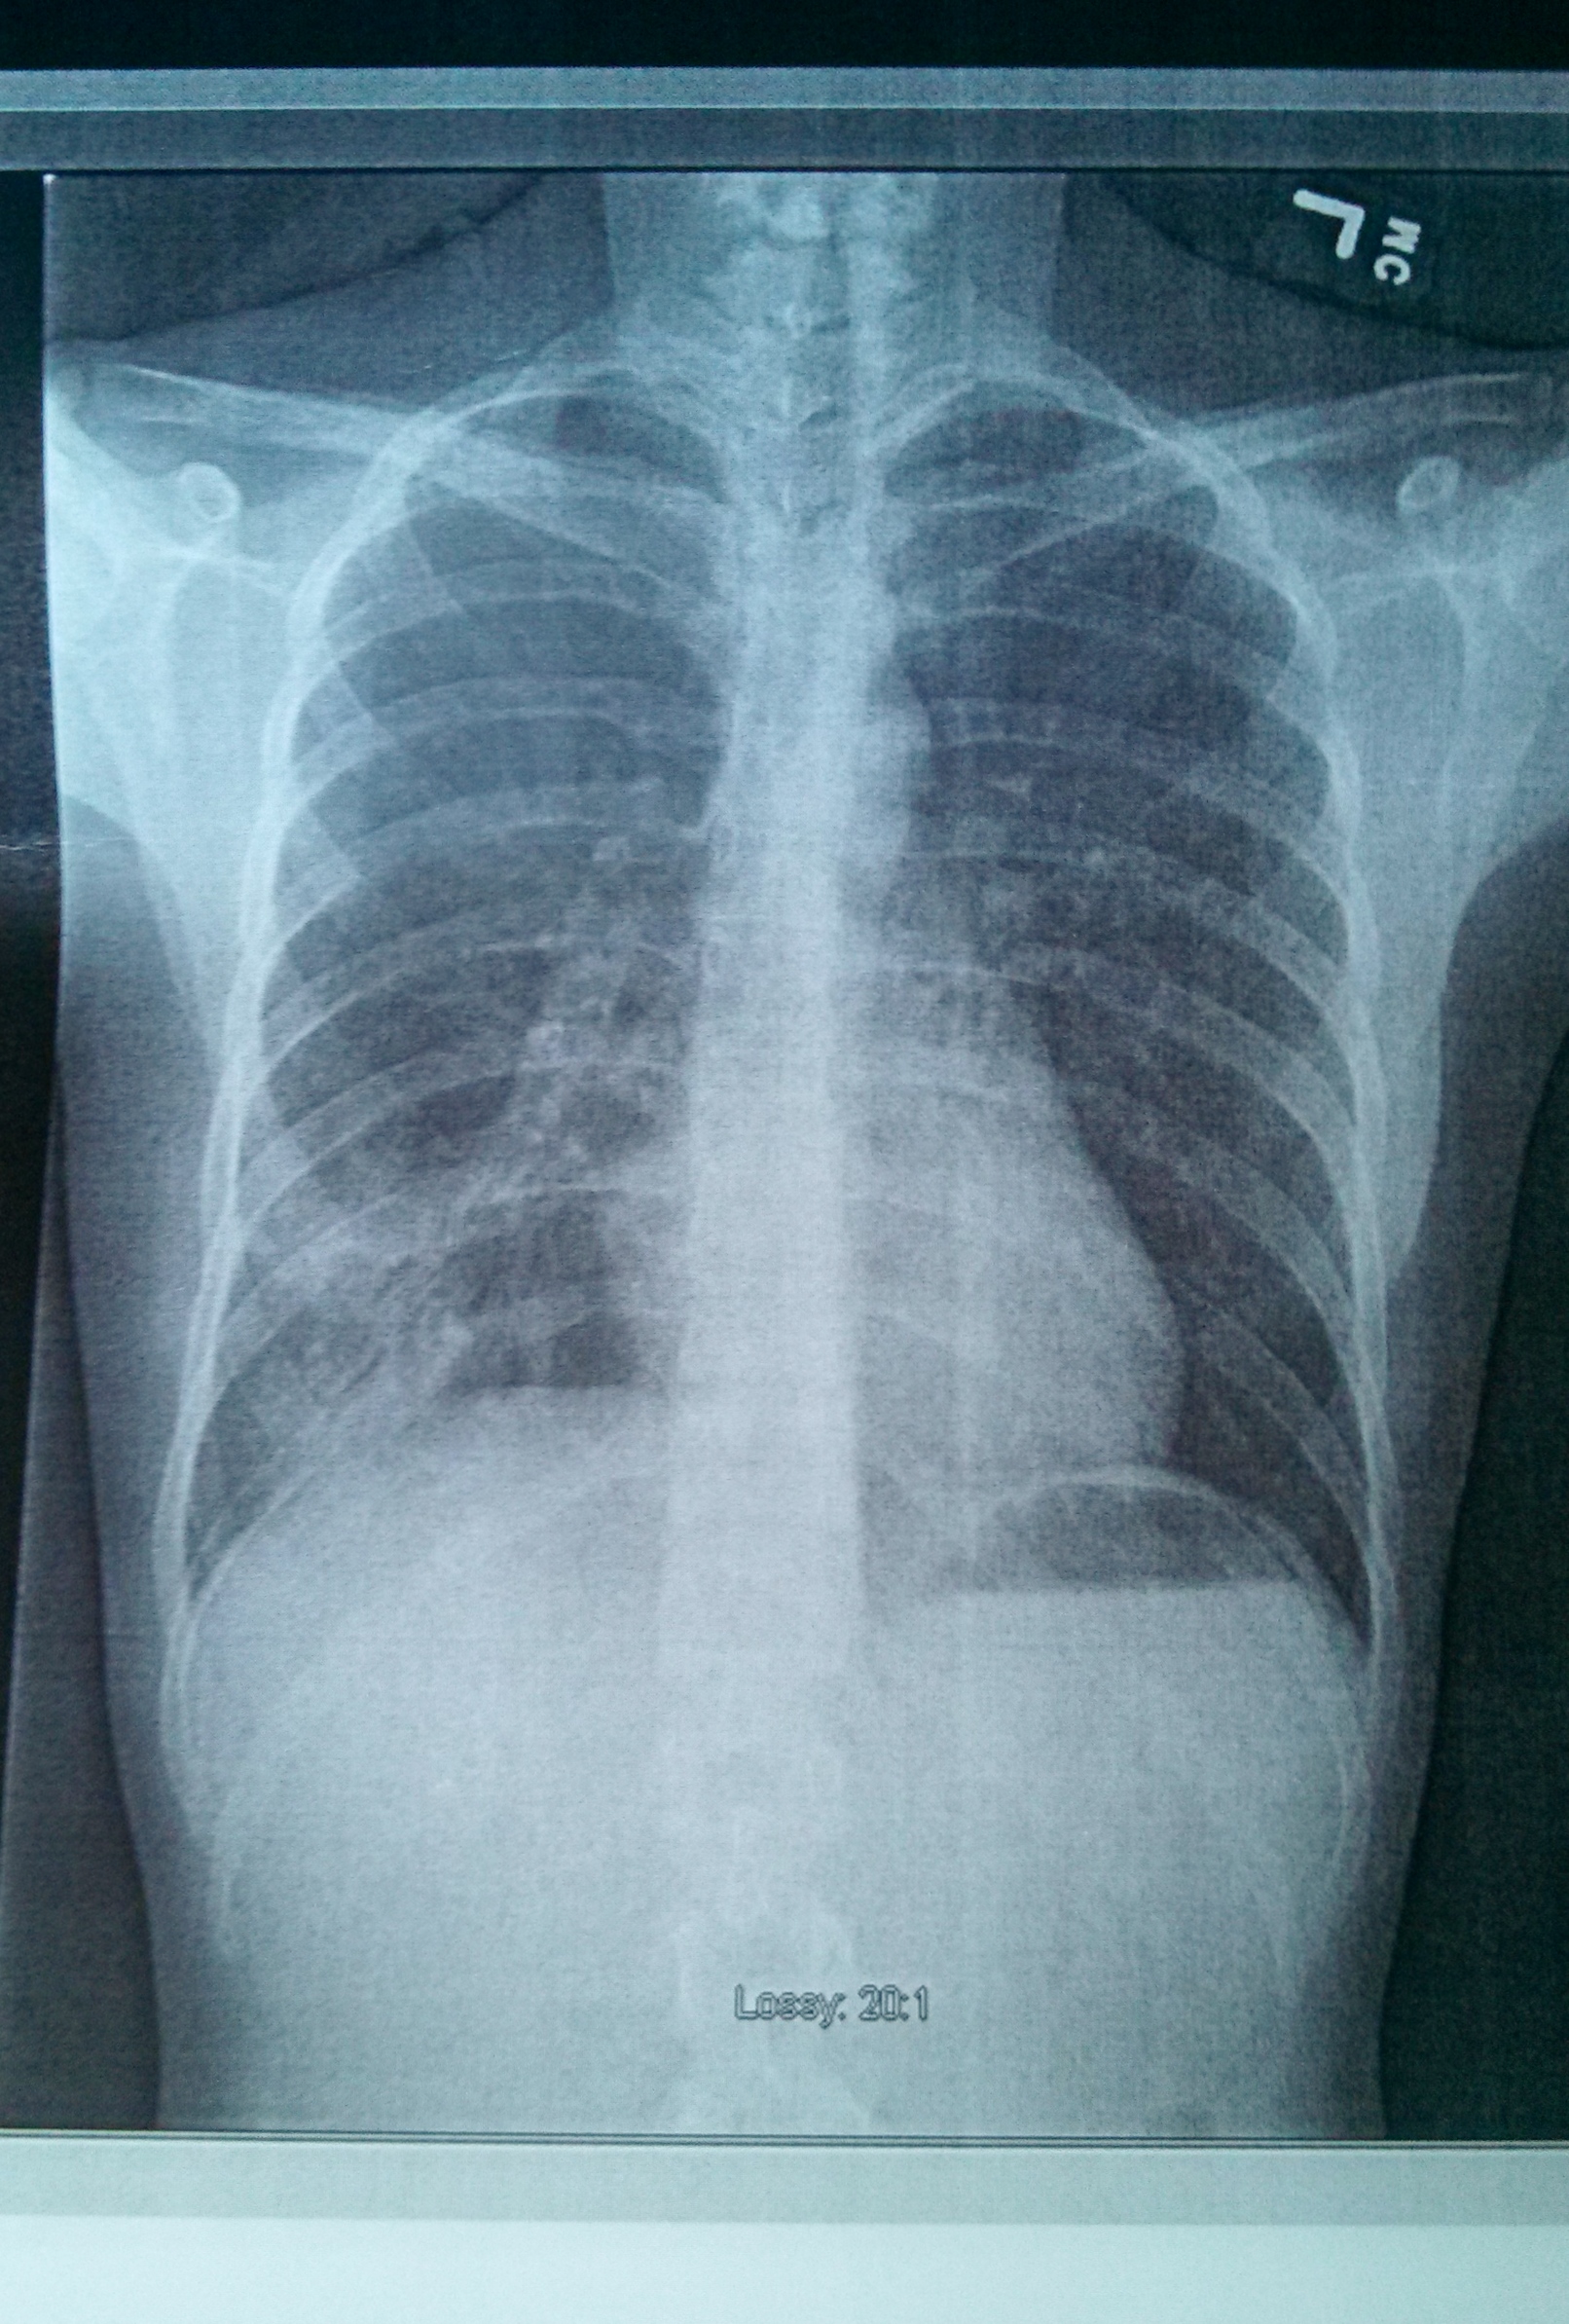

SO, in case you were wondering if I was still around… I have been in bed, sick as a dog, for a solid week! Jay brought me to the urgent care clinic a few days ago, where I had an exam and a chest x-ray done…to find out that I have…

Pneumonia! Ick.

(How do you like my innards?)